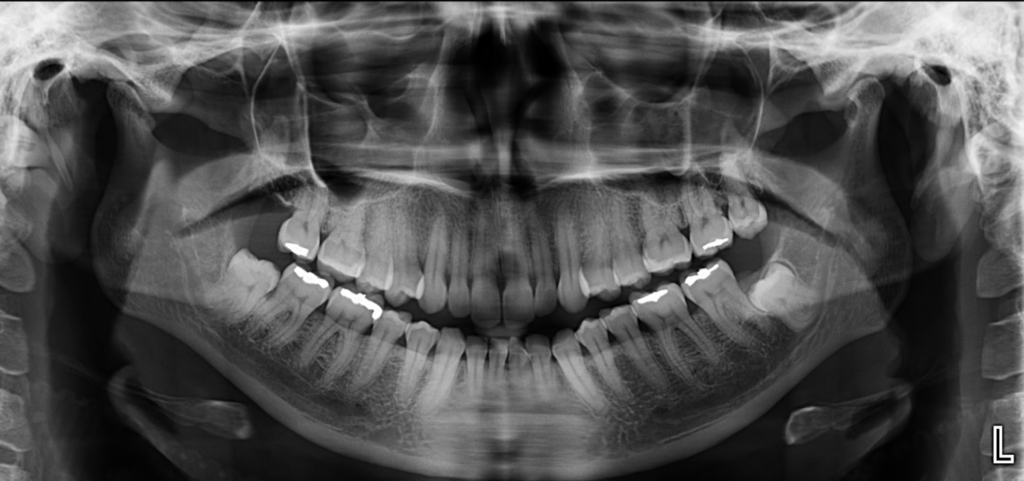

Paciente femenina acude a la sede de IDM- Miraflores para una tomografía computarizada para la evaluación de terceras molares. A la evaluación de la radiografía panorámica se observa aplanamiento del contorno condilar bilateral a predominio del lado derecho,

neumatización de ambos senos maxilares, múltiples restauraciones coronarias, ausencia de la pieza 18 y la impactación de la pieza 38 que a su vez presenta dilaceración de la raíz mesial e hipercementosis.

Radiografia Panorámica